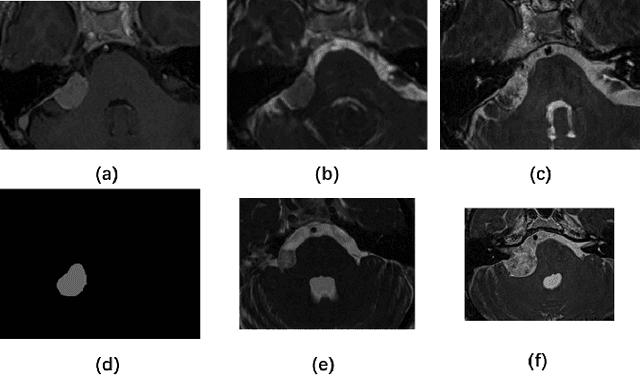

This paper proposes an unsupervised cross-modality domain adaptation approach based on pixel alignment and self-training. Pixel alignment transfers ceT1 scans to hrT2 modality, helping to reduce domain shift in the training segmentation model. Self-training adapts the decision boundary of the segmentation network to fit the distribution of hrT2 scans. Experiment results show that PAST has outperformed the non-UDA baseline significantly, and it received rank-2 on CrossMoDA validation phase Leaderboard with a mean Dice score of 0.8395.